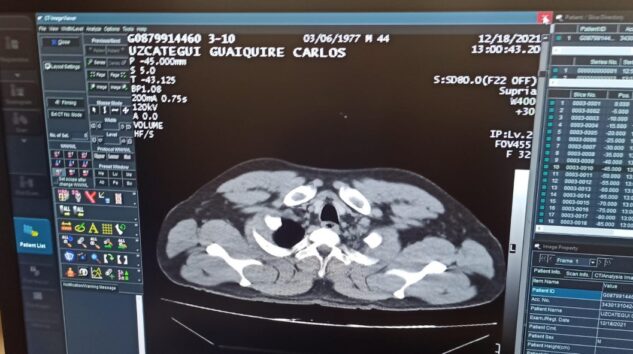

C.M.U.G’un hastanede yapılan tomografi kontrolünde mide ve bağırsaklarında 12 adet kapsül kokain tespit edilmesini üzerine, ameliyata alındı. C.M.U.G., tedavi gördüğü hastaneden taburcu edildikten sonra Cumhuriyet Savcılığı’na sevk edildi.